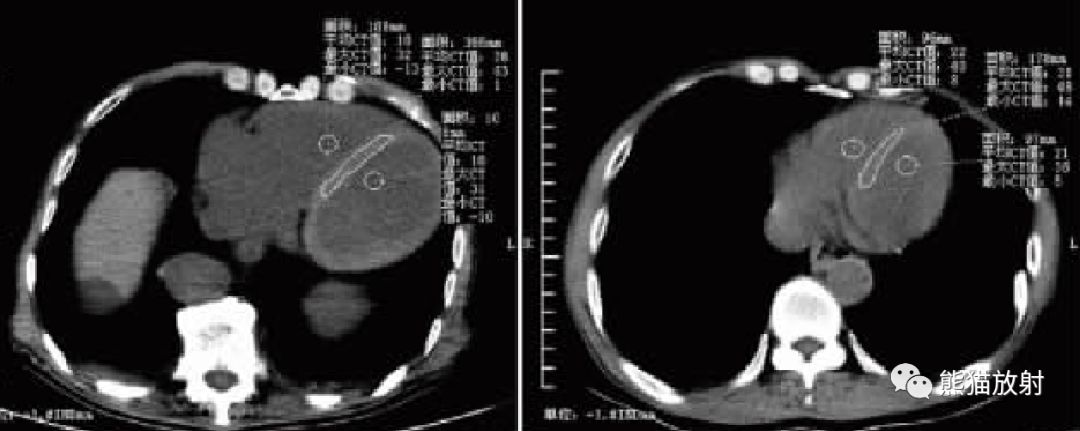

心室的CT密度与血液中Hb的浓度呈密切的正相关,而室间隔由心肌纤维组织构成,在排除心内膜疾病的情况下,其密度较少发生改变。

在胸部CT平扫图像上如果可以分辨出室间隔则提示有严重贫血的存在。

贫血程度与室隔差值存在相关性,血液Hb浓度的减低程度越严重,室间隔征越明显,室隔差值越大。

CT平扫诊断贫血的最佳定量方法是左心室和室间隔之间的差值。

在选择ROI 时尽量选择靠近室间隔的位置,减少乳头肌的影响。